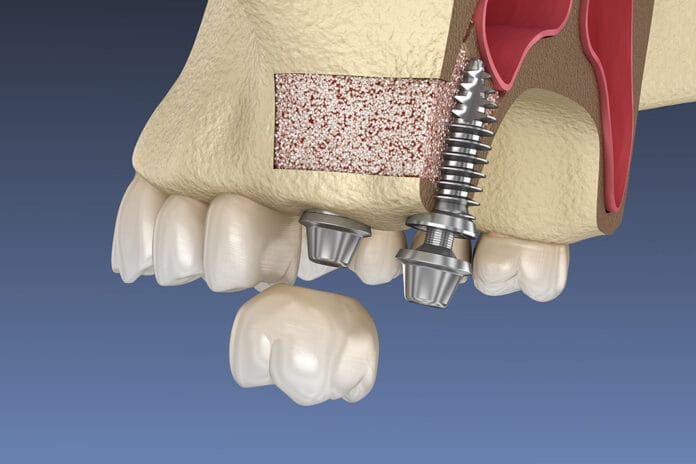

A Hygienists’ Overview of Sinus Augmentation and Its Role in Implant Placement

When a posterior maxillary tooth has been lost, a physiological process begins that can cause the alveolar ridge to resorb. This process can result...